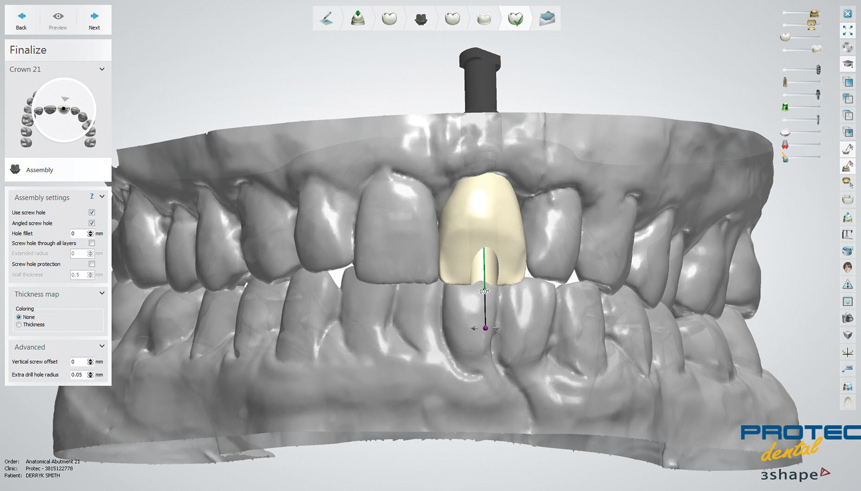

Fig 2. Lateral view (digital) showing articulated casts and buccal angulation of implant.

Figure 2

Fig 3. Front view (digital) showing articulated casts and position of access opening on facial aspect of crown if implant angulation is not “corrected.”

Figure 3